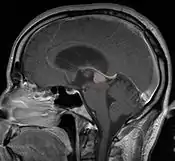

Пинеалома — опухоль головного мозга, исходящая из шишковидного тела. Это гетерогенная группа новообразований, локализующихся в пинеальной области (задние отделы III желудочка, область цистерны четверохолмия) и имеющих различное происхождение. Развитие пинеаломы может быть связано с опухолевой трансформацией пинеалоцитов, астроцитов или гоноцитов[2][3]. Опухоль, развившаяся из пинеалоцитов, в зависимости от степени дифференцировки носит название пинеоцитома, пинеальная паренхиматозная опухоль промежуточной дифференцировки, пинеобластома. Опухоли астроцитарного происхождения имеют типичное строение. Наиболее характерным для астроцитомы является медленный, инфильтративный рост.